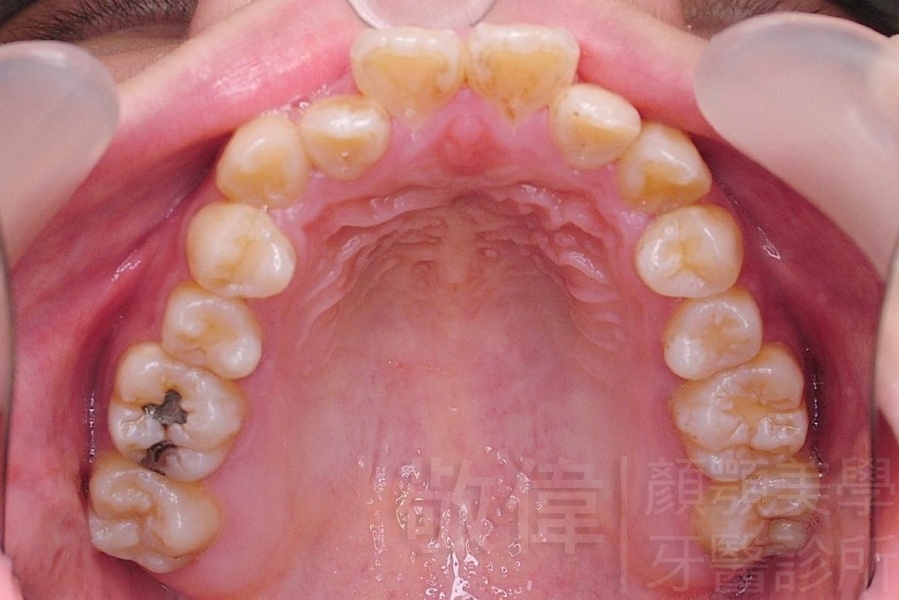

齒顏矯正/戽斗、亂牙、爛牙,變身 免植牙的健牙美女

<個案說明>

變臉矯正,原來戽斗妹跟大歪臉變成自信正妹

經由本院3D數影X光影像儀分析、與3D齒顎顏矯正技術,再配合口腔顎面正顎專科醫師施以正顎手術治療,雙方共同合作,使患者臉部外觀有很好的改善,大歪變小歪,產生了天南地北的大改變,她的人生也整個變得不一樣。